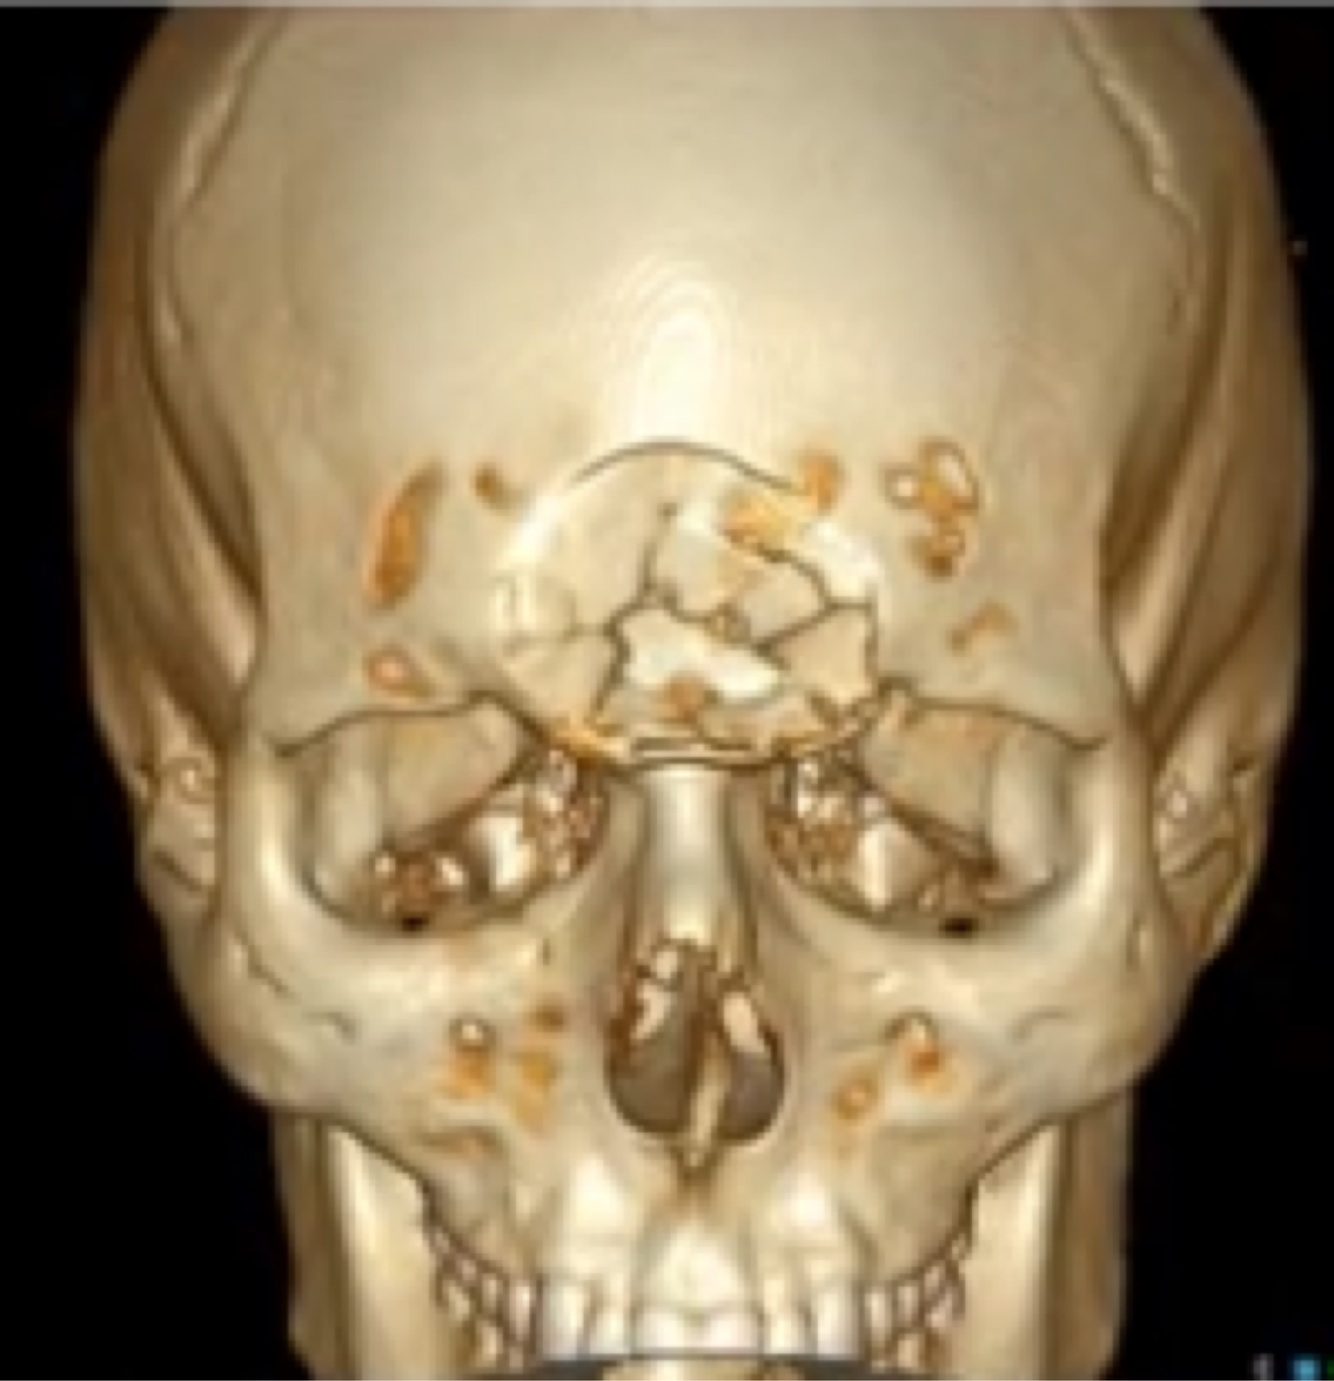

Tipo de fratura a seguir:

A